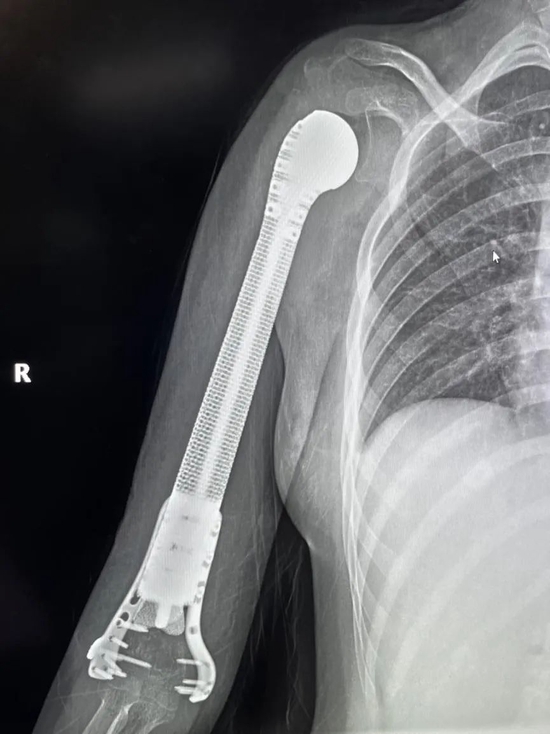

术前,经精密计算机辅助设计、影像学数据镜像反求和钛合金3D打印,假体的3D打印仿骨小梁端和截骨端可以完美贴合,使骨长入得以实现,达到生物重建效果。这样既保留了关节,也减少假体松动的发生率。同时空隙结构利于软组织长入。

手术当日,在麻醉科配合下,杨团民主任团队密切协作、精细操作,依次完成肿瘤切除、3D打印假体植入、软组织重建系列操作。

历时3小时,顺利完成医院首例3D打印肱骨假体治疗肱骨骨肉瘤手术。目前,小欣全身状况良好,正在进行积极的功能锻炼,力争尽早实现正常生活。